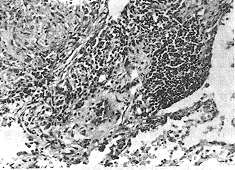

图1 霉草尘肺 肺泡腔内多数巨噬细胞,个别在其胞浆内见有霉菌孢子,间质纤维化,细支气管亦有增生 HE×100

右下叶肺,实质内有灰白色界限不清的实变区(2cm×1cm),余肺有散在1~2mm病灶,质软,轻度肺气肿。镜下见部分肺泡腔内积大量巨噬细胞,周围明显纤维性增生,间质内尚有淋巴细胞等浸润并伴胶原纤维增加,部分细支气管腔狭窄,周围亦有纤维化,个别部位见有类结节状病灶,由胶原纤维、毛细血管、炎细胞和纤维母细胞等混合构成。